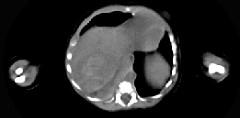

男,5天,上腹部膨隆,CT所见如图,最可能的诊断是()A.原发性肝癌B.肝母细胞瘤C.肝血管瘤D.肝脓肿E.肝转移瘤

问题 男,5天,上腹部膨隆,CT所见如图,最可能的诊断是()

选项 A.原发性肝癌 B.肝母细胞瘤 C.肝血管瘤 D.肝脓肿 E.肝转移瘤

答案 B